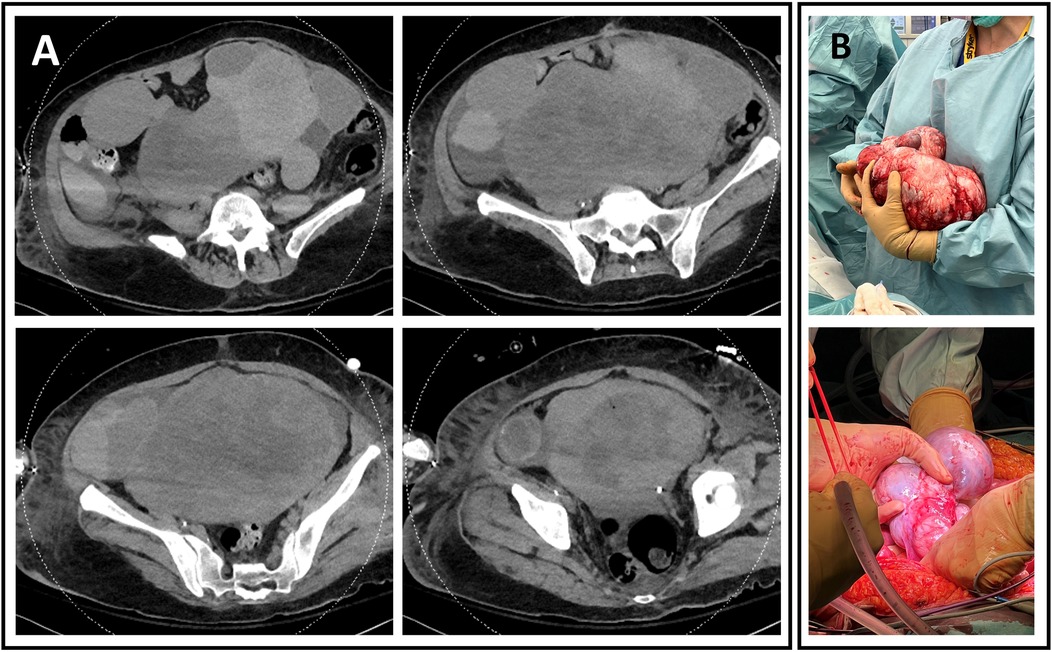

A 60-year-old woman was admitted to our ICU after a cardiac arrest. Her history was largely unknown aside from active smoking. According to her husband, she had progressive dyspnea for several weeks but sought no medical advice. One night, she coughed up blood and collapsed. Her husband initiated CPR; paramedics arrived 15 min later and provided advanced life support. Return of spontaneous circulation (ROSC) was achieved after 10 min. The initial rhythm was asystole, with a no-flow time of 15 min and a low-flow time of 10 min. She was intubated, ventilated, and stabilized with epinephrine. An electrocardiogram showed sinus tachycardia without signs of acute coronary syndrome. A CT scan ruled out intracranial hemorrhage and pulmonary embolism, but it revealed a large necrotic mass near the adnexa with ascites (Figure 1), hypodense liver lesions, and bilateral pleural effusions with lower lobe atelectasis.

Figure 1. (A) Abdominal CT scan showing a large, heterogeneous, fleshy, and hypervascularized cystic mass measuring 27.2 cm wide, 14.1 cm deep, and 21.7 cm high. (B) Perioperative excision of two large multiloculated cystic masses. (Top) Left mass, weighing 2,932 g, measuring 27 cm × 20 cm × 20 cm. (Bottom) Right mass, weighing 436 g and measuring 15 cm × 8 cm × 5 cm.